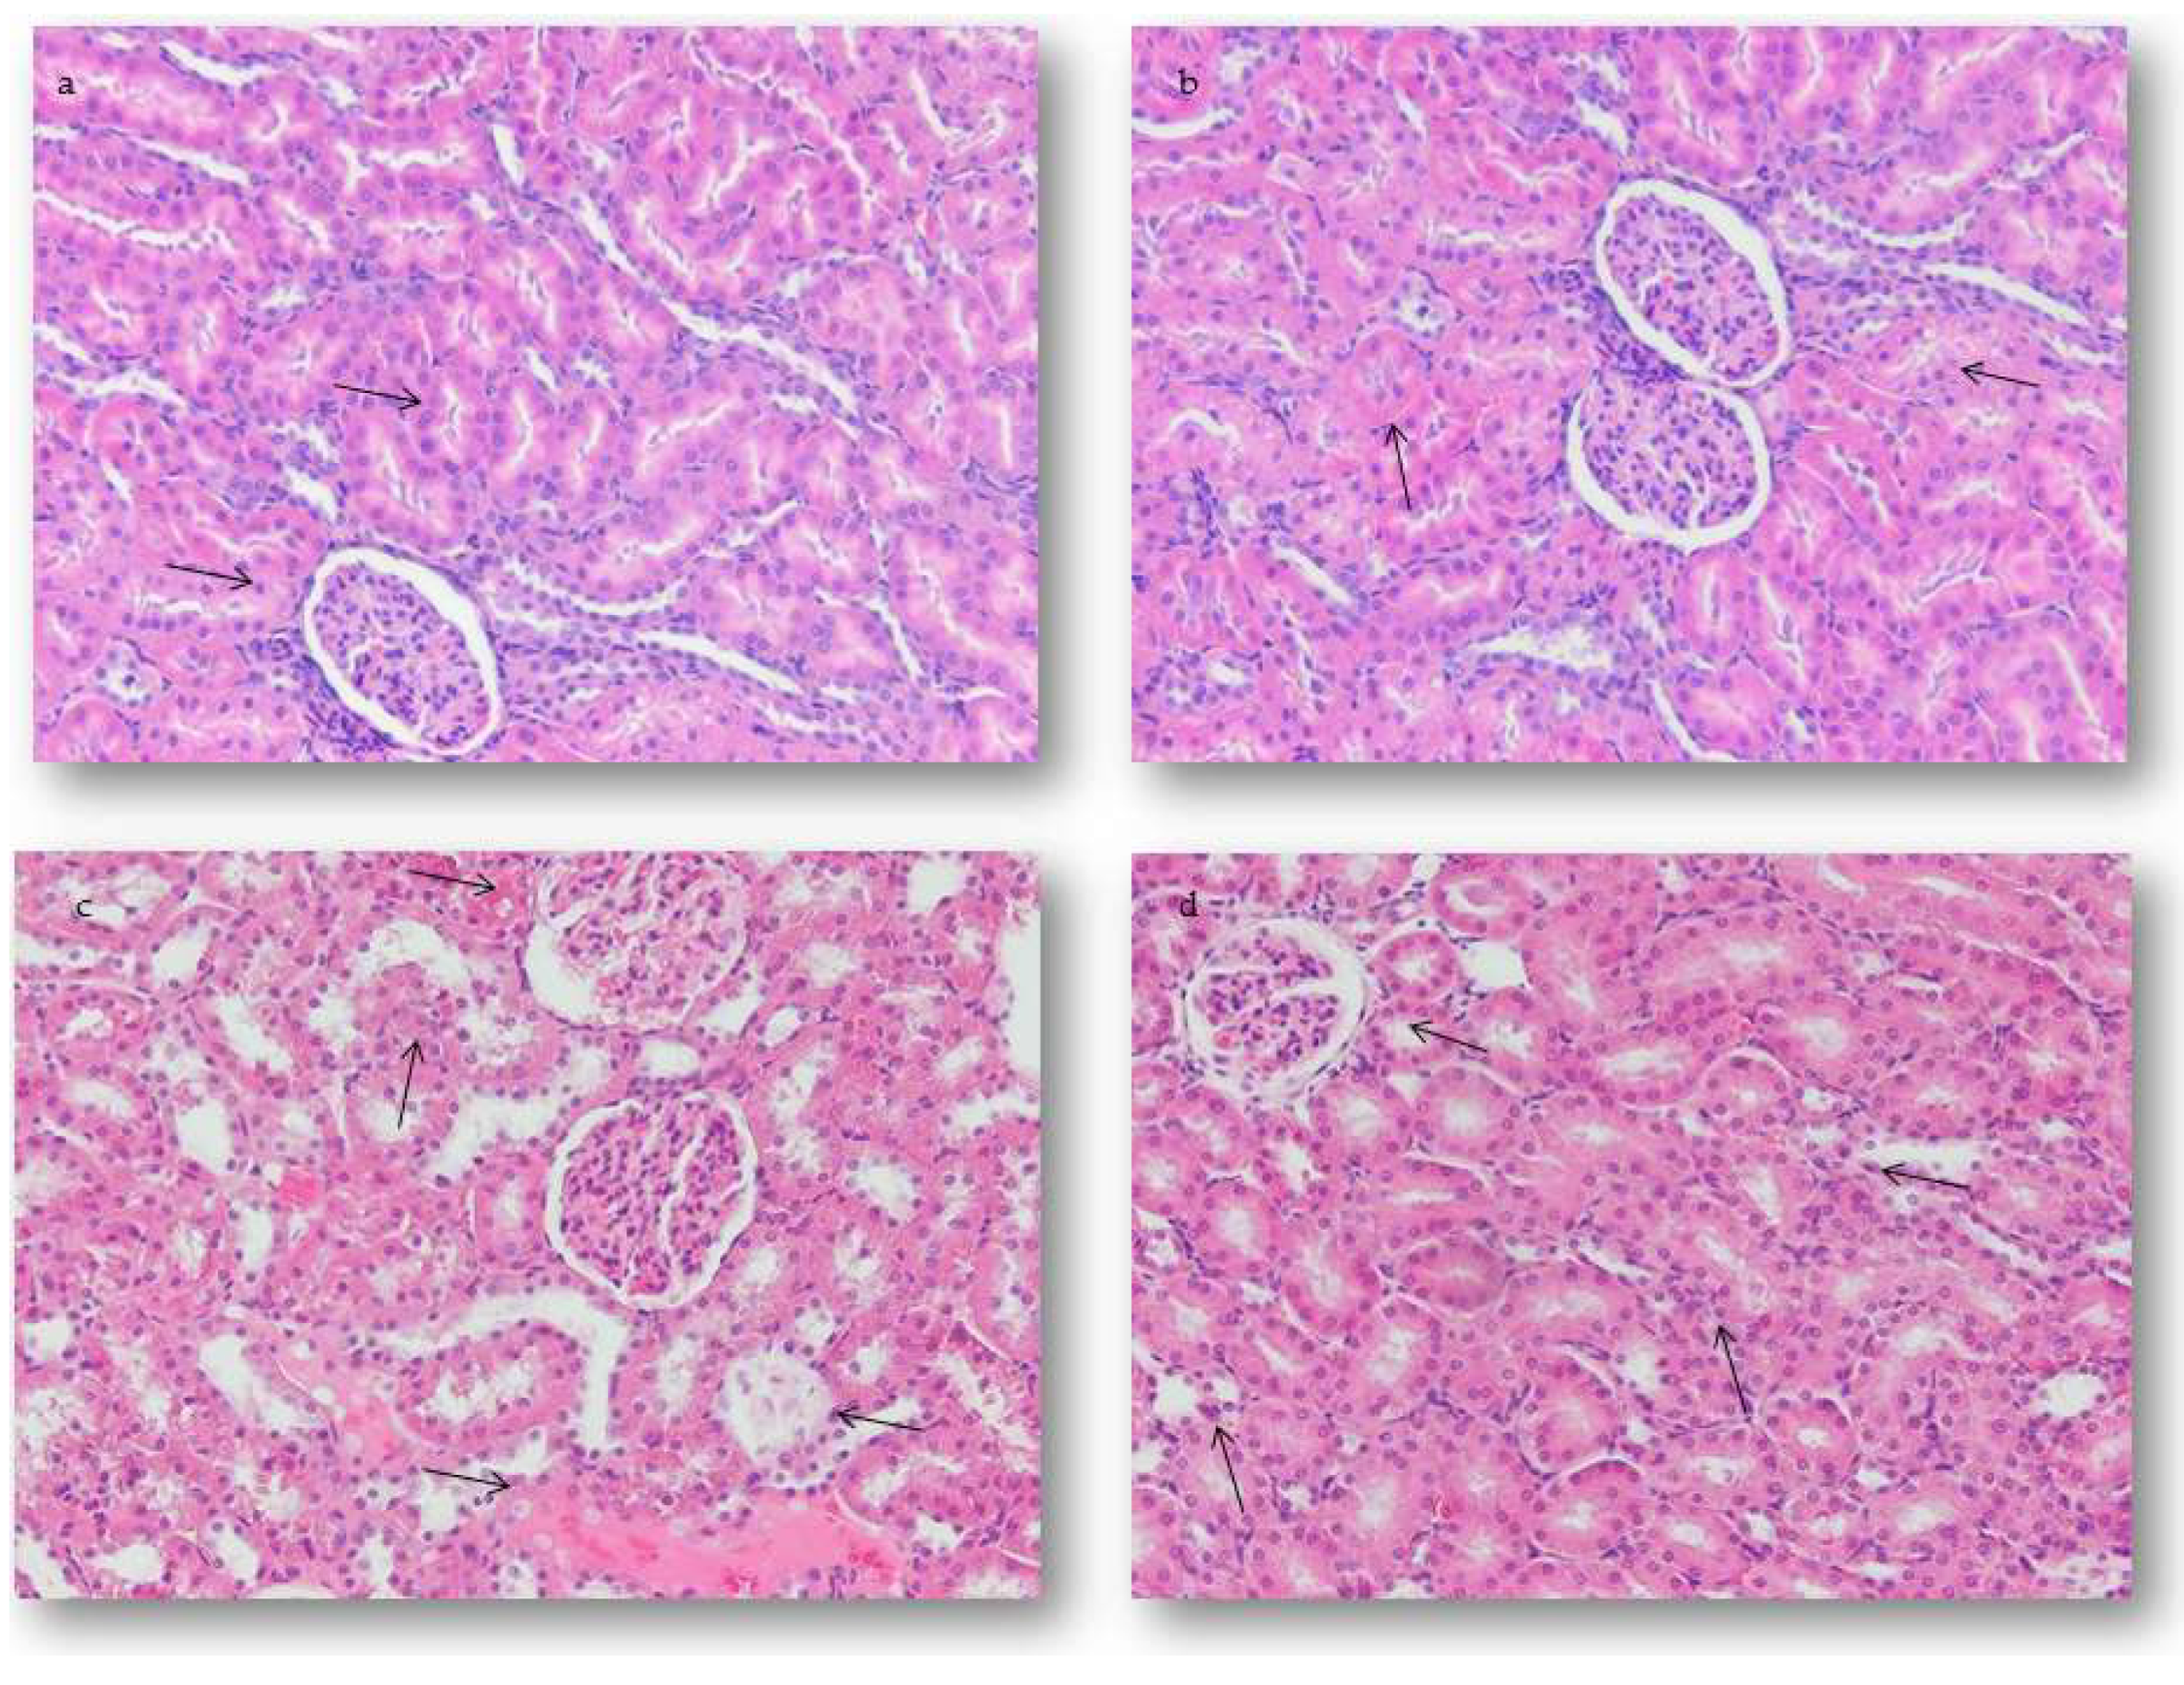

2.4.2. Renal Alterations

2.5.2. Quantification of Renal Alterations